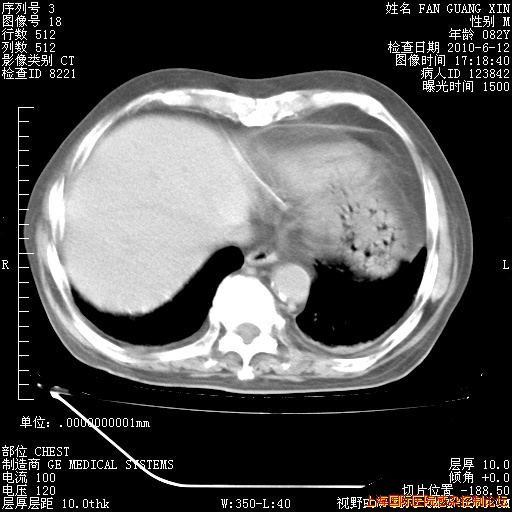

今天CT

整整相隔30天的肺部CT好像有所好转啊。甲强龙减量第3天,需要观察体温。